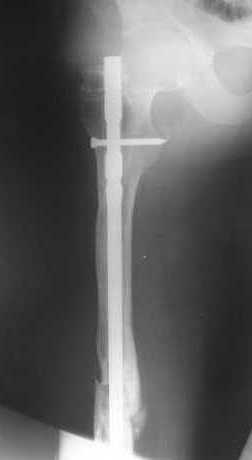

Пациенту М., 30-ти лет, 1,5 года назад в одной из московских больниц был выполнен остеосинтез бедренной кости штифтом UFN (диаметр штифта 9 мм).

К нам больной поступил с признаками ложного сустава бедренной кости, перелома

штифта и дистального блокирующего винта (images 1,2,3).

27 марта выполнено удаление блокирующих винтов (сломанный винт пришлось высверливать цапфен-бором), сломанного штифта (дистальный фрагмент удален через канал, образованный разверткой из коленного сустава - image 4),

рассверливание костно-мозгового канала, реостеосинтез штифтом UFN (при проведении штифта в дистальном отломке мы использовали поляризующий винт, диаметр штифта 10 мм). После операции в связи гемартрозом дважды (на 1 и 3 сутки) выполняли пункцию коленного сустава. Сейчас признаков скопления жидкости в полости сустава нет. Послеоперационные рентгенограммы - images 5, 6, 7.